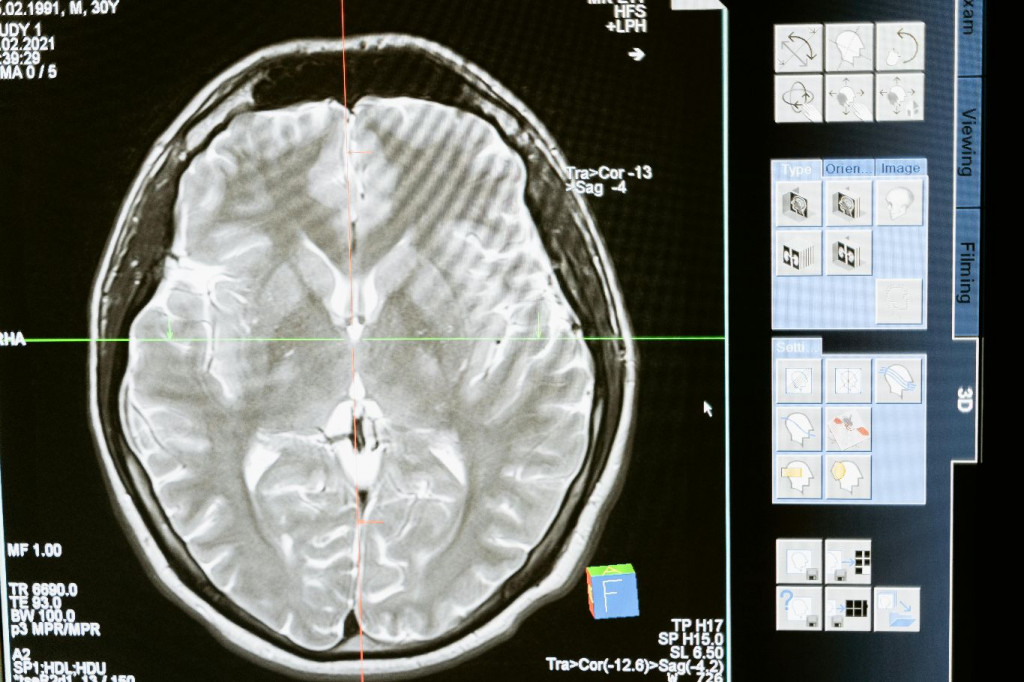

Tijekom jedne epizode programa britanske "ITV", stručnjaci su analizirali snimke magnetske rezonance koji su pokazali kako mozak adolescenta reagira na ugodna iskustva poput listanja "TikToka" ili "Instagrama".